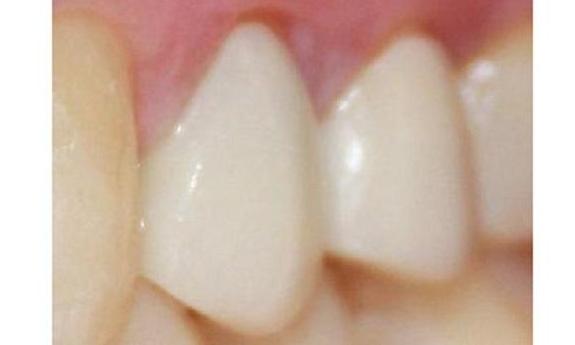

This patient had a discolored tooth that also had some decay. The tooth was properly restored with porcelain crown and the patient left extremely happy!